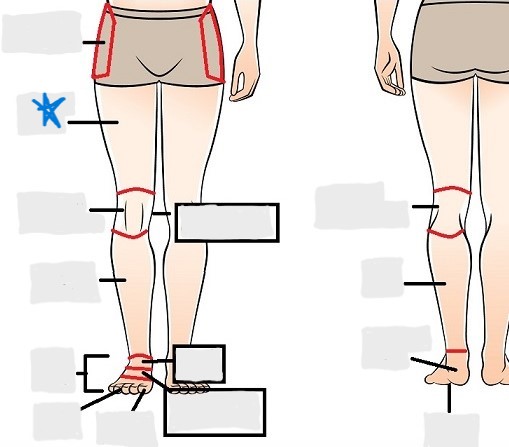

appendicular

coxal

femoral

patellar

popliteal

crural

sural

peroneal

calcaneal

plantar